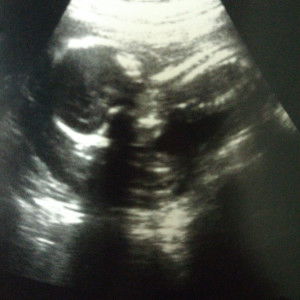

Amin .. sis dan husb boleh cuba amalkan acid folic .. Alhamdulillah , sy amalkan acid folic atas nasihat farmasicst , now sy pregnant 23w .. apa pon kita kna usaha dan ikhtiar .. try n error .. semoga kita sma² dimurahkan rezeki

try jus mamom hope sis.. insyaallah dengn izin allah..kte iktiar dia yg tentukan..sy try 2botol alhamdulillah rezeki sy skng dh 21w